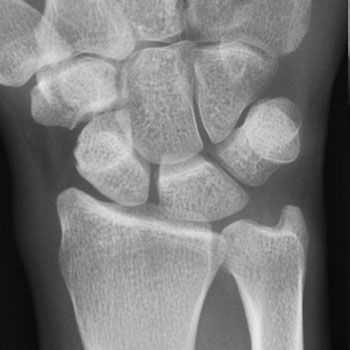

- Для подтверждения диагноза болезнь де Кервена может потребоваться рентген. На полученных снимках можно заметить наличие кальциноза в области первого костно-фиброзного канала;

- Рентгенография: для уточнения диагноза, иногда применяется рентгенография области лучезапястного сустава в прямой проекции. На рентгенограмме можно увидеть обызвествление в зоне первого костно-фиброзного канала.